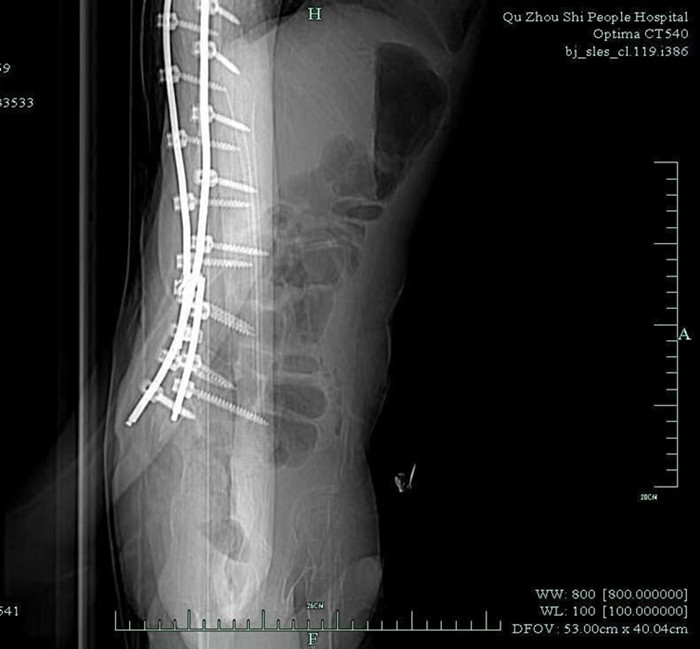

早就收過(guò)病危通知書的小徐,由于沒(méi)有肌肉力量的支撐,大部分骨骼被擠壓變形。體重不足40公斤的他,幾年前因?yàn)榧怪鶄?cè)彎,靠著打進(jìn)身體里的37枚鋼釘,才勉強(qiáng)能在輪椅上坐穩(wěn)。

鞘內(nèi)注射是神經(jīng)內(nèi)科醫(yī)生的基本操作,本身并沒(méi)有多大難度。但由于小徐長(zhǎng)年疾病導(dǎo)致脊椎側(cè)彎,椎管變得彎彎曲曲,還有37根鋼釘橫亙其中,這讓原本并不復(fù)雜的注射治療變得十分困難。